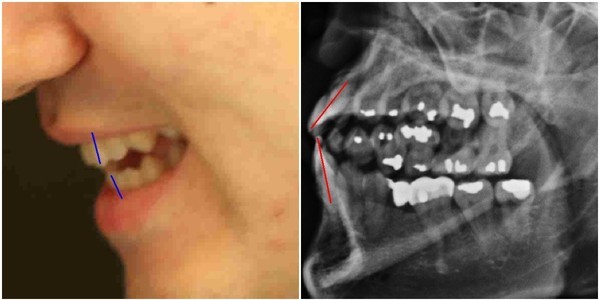

- ▲ 박주신씨 명의의 자생병원 엑스레이와 주신씨의 실물사진 비교. ⓒ 뉴데일리DB

‘박주신씨 병역비리 의혹’을 제기하다가 공직선거법 위반(낙선목적 허위사실 유포) 혐의로 재판을 받고 있는 ‘양승오 박사 재판’ 피고인들이, 주장의 근거로 들고 있는 주요 증거 가운데 하나가, 박주신씨 명의의 엑스레이 속 피사체의 치아상태를 볼 수 있는 구외 엑스레이(이하 치아 엑스레이)다.

양승오 박사 등에 대한 검찰의 수사가 진행되던 지난해, 이 사건 피고인들은 박주신씨 치아 X-Ray를 근거로, 박주신씨의 신체를 촬영했다는 X-Ray 속 피사체가 제3의 인물일 가능성을 주장했다.

문제의 액스레이는 박주신씨가 병역변경처분을 받기 위해 자생병원에서 MRI를 촬영하면서 함께 찍은 것으로 알려져 있다.

피고인들이 치아 X-Ray를 근거로, '피사체 바꿔치기' 의혹을 강하게 제기한 이유는, X-Ray에 나타난 치아의 상태가, 도저히 20대 중반 청년의 것이라고는 보기 힘든 특징을 갖고 있었기 때문이다.

주신씨 치아 X-Ray 사진을 보면, 치아 상태가 매우 불량하다는 사실을 알 수 있다. 치아 3개는 발치된 채 방치돼 있고, 아말감으로 때운 치아가 무려 14개에 달한다.

- ▲ ▲치과의사 문씨가 촬영한 것으로 알려진 박주신씨 명의의 치아 엑스레이 자료. ⓒ 차기환 변호사

- ▲ 박주신씨 치아 엑스레이 분석자료. ⓒ 뉴데일리DB

아말감(Amalgam) 치료는 변색 등 여러 가지 단점을 갖고 있어 사용빈도가 크게 줄고 있다는 것이 치과의료계의 공통된 평가다.

서울 방배동에 사는 중산층 청년이, 치과의사는 물론 환자들도 기피하는 아말감을 이용한 치과 치료를 이처럼 많이 받았다는 것은, 쉽게 받아들이기 어렵다는 것이 양승오 박사 재판 피고인들의 지적이다.

피고인들은 주신씨 명의의 치아 엑스레이를 보면, 하악 좌측 1소구치(아래쪽 좌측 첫 번째 작은 어금니)까지 아말감으로 치료한 사실을 확인할 수 있다며, 이런 경우는 매우 드물다고 지적하고 있다.

이 사건 피고인 중 한명인 치과의사 김우현씨는, 주신씨의 영구치가 맹출을 시작했을 것으로 추정되는 1990년대 중반 이후, 젊은 사람이 1소구치를 포함한 구치부 치아 전체를 아말감으로 치료했다고 보기엔 무리가 있다고 입장을 밝혔다.

치의학 박사 C씨는 뉴데일리와 기자와의 인터뷰에서 “주신씨의 전체적인 치료 상태를 보면, 소위 말하는 '야매'로 했을 가능성이 높다”는 의학적 소견을 내놓기도 했다.

“(주신씨의 것이라고 알려진 구외 X-Ray 사진을 보면) 최근 국내에서 교육받은 치과의사의 치료라고 생각할 수 없을 정도.”

“(주신씨 구외 X-Ray 사진 상의) 45번, 46번 보철치료 및 치아 상실 문제도 마찬가지다. 보철물로는 상당히 저렴한 비귀금속 합금을 사용한 것으로 보인다. 37번 치아는 아예 없는 상태로 방치돼 있다.”

“박주신씨의 가정환경을 고려하면, 이런 치료를 받았을 가능성은 1%도 안 된다. 서울 방배동에 거주했던 중산층 이상의 가정에서는 흔치 않은 상황.”

주신씨의 치아 아말감 치료와 관련돼, 김우현씨는 “혹자는 아말감 치료를 10개 이상 한 게 무슨 대수냐? 하면서 무시하는 경향이 있지만, 이는 모든 인과관계와 사실들을 무시하려는 것”이라고 비판했다.주신씨의 치아 X-Ray 사진 상에 나타나는 의문들은, 양승오 박사 등이 주신씨의 병역비리 의혹을 제기하게 된 핵심 요인 중 하나였다.